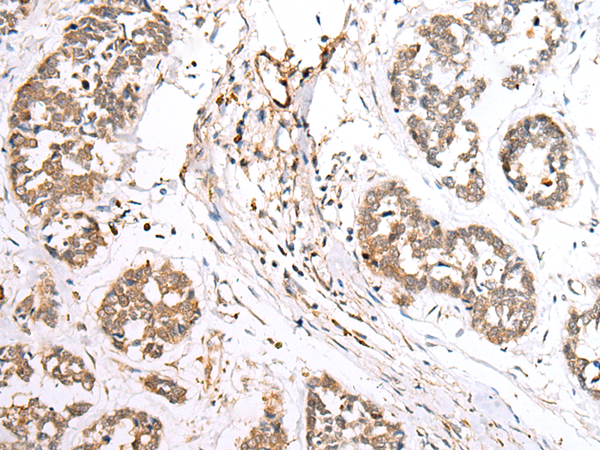

IHC positive control: |

Human tonsil and human esophagus cancer |

IHC Recommend dilution: |

30-150 |